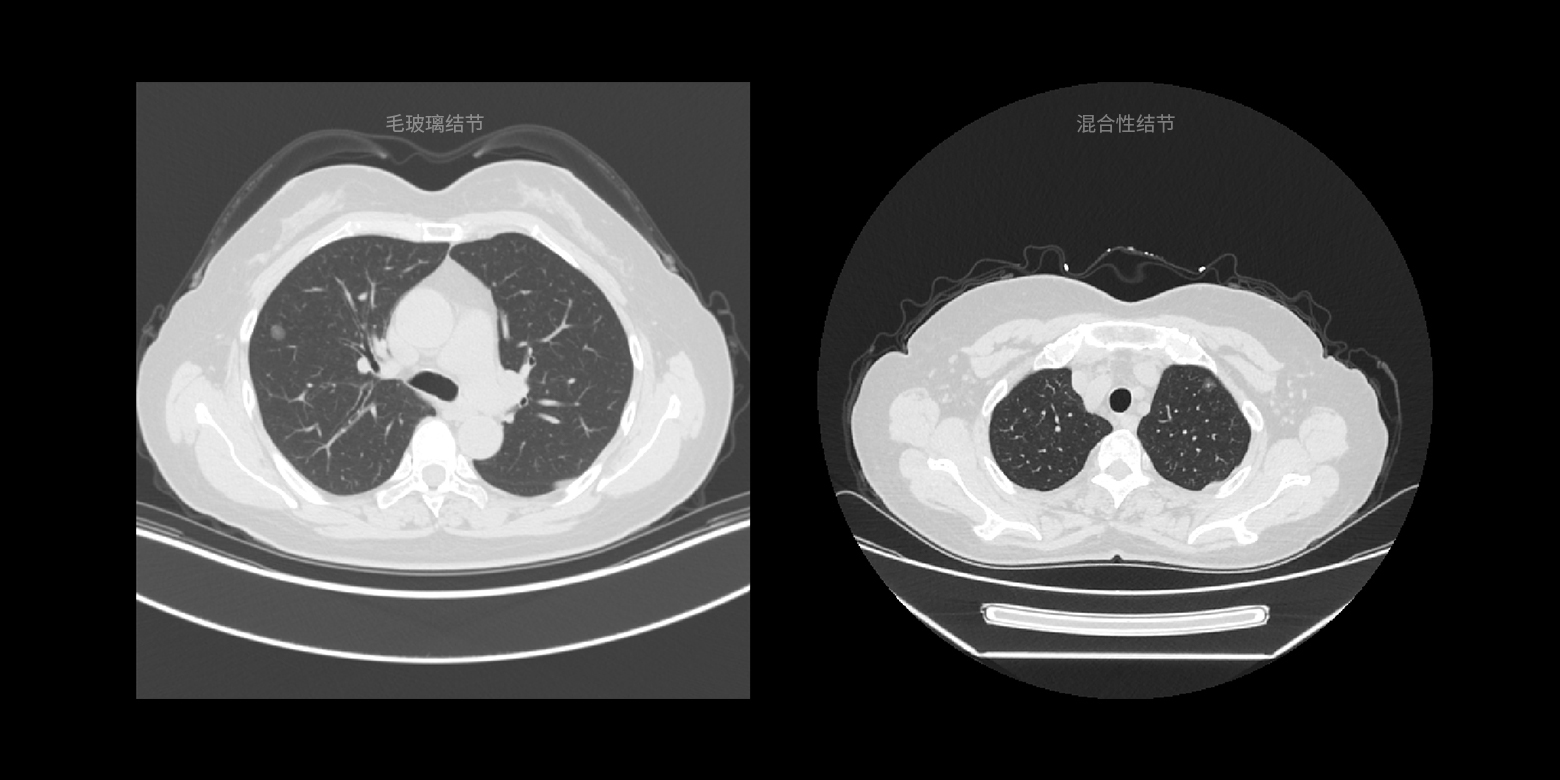

病灶类型鉴别

结合国际通用的诊断指南以及顶级医生的诊断经验,对临床诊断起到关键作用的病灶类型进行快速鉴别,降低相似病灶的误诊概率。